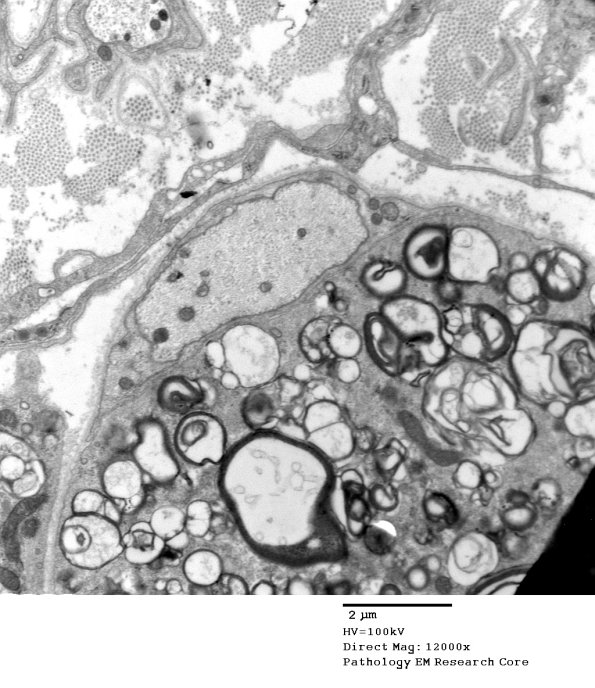

3B2A,B A naked axon surrounded by macrophage processes containing myelin debris. (electron micrographs)